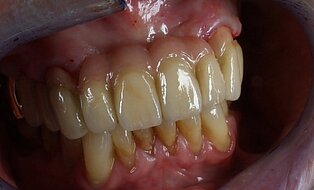

Meisterarbeit von Peter Dengel

Vom Langzeitprovisorium zur TEK 1 Arbeit